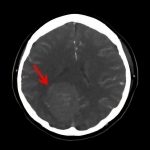

断層撮影

摘出 後